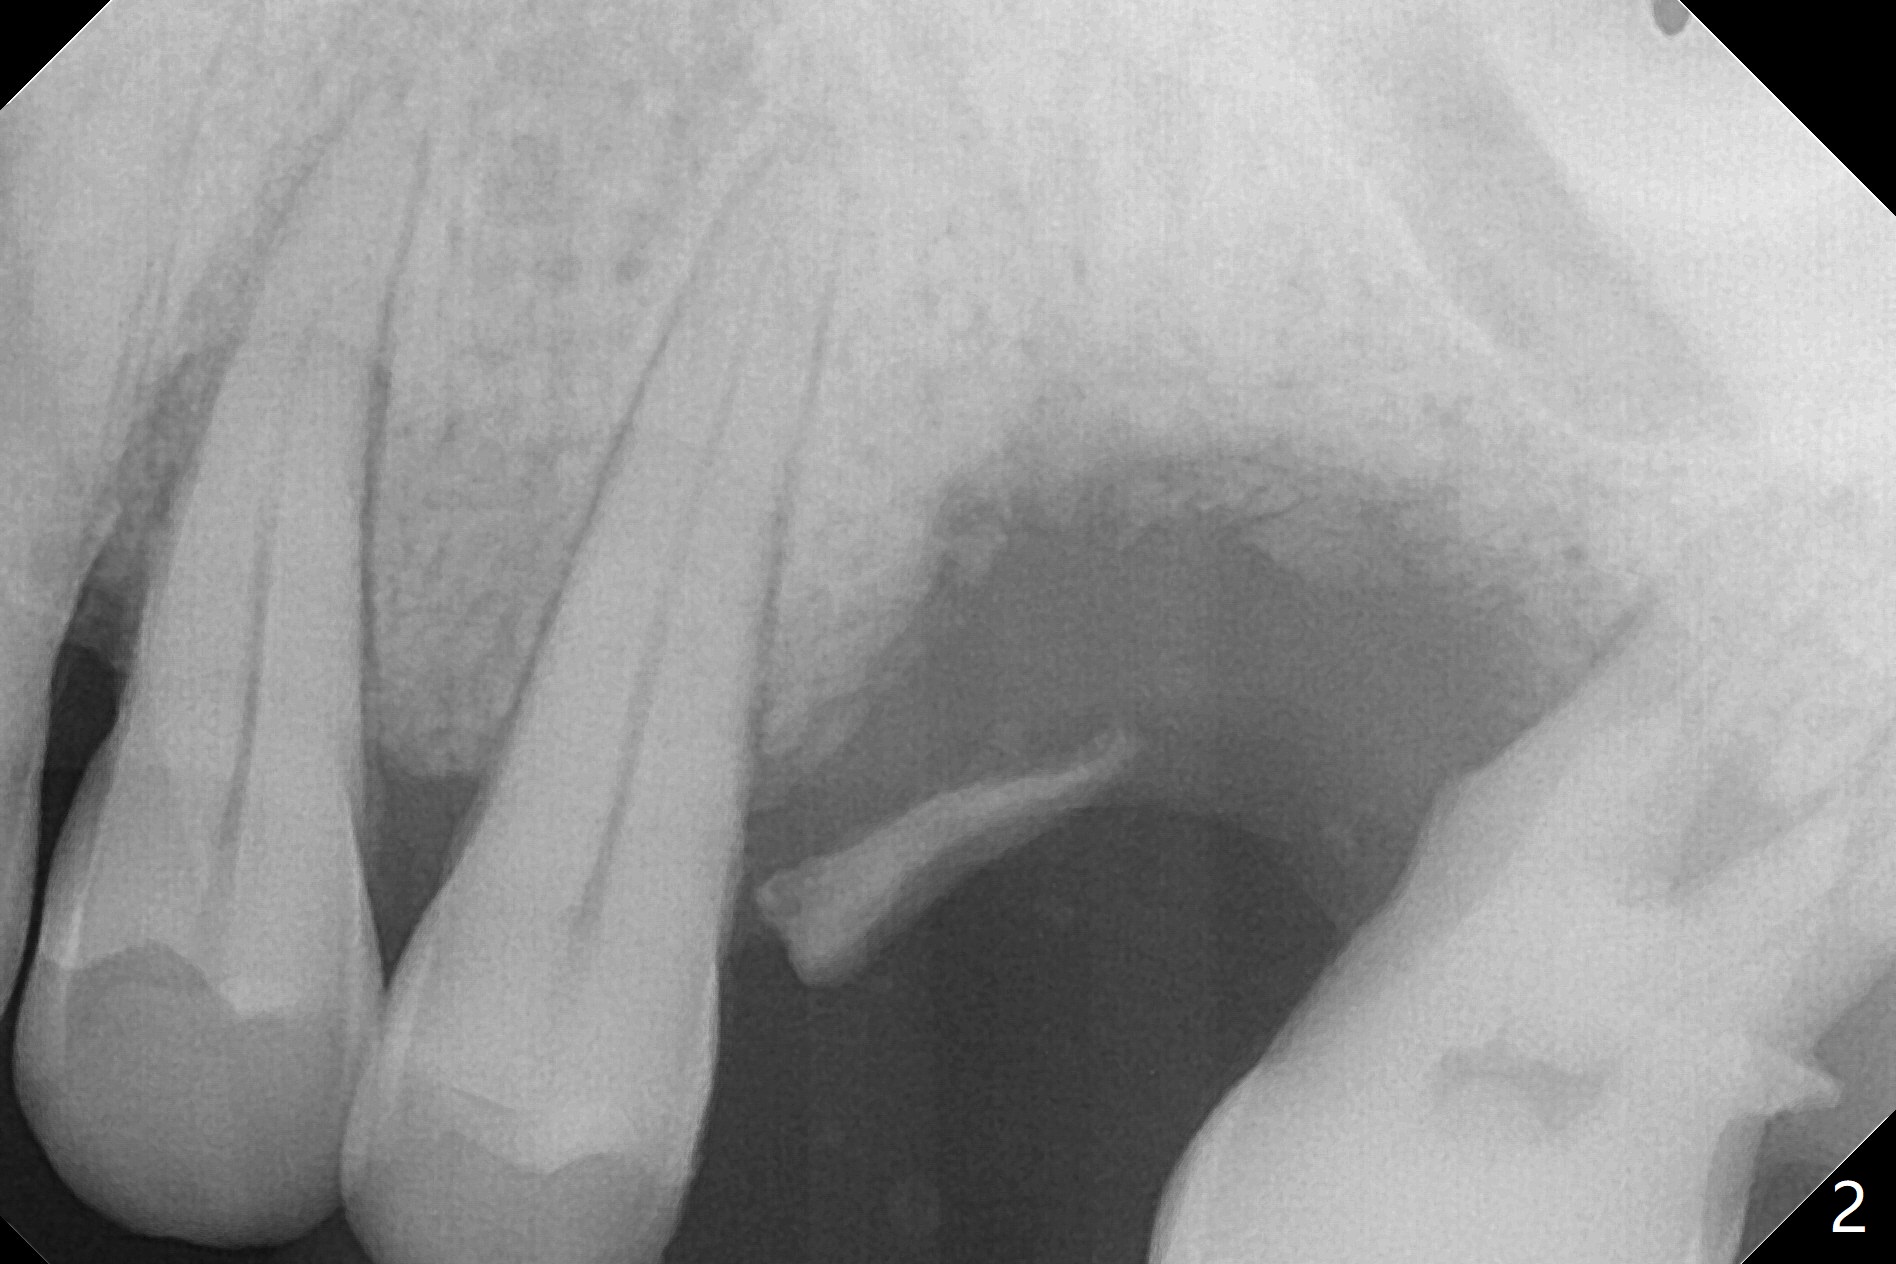

50岁男两年前不肯拔牙左上6(图一),现在要求及早拔除植骨(图二),几个月后与左下7一起植牙。我们准备深洗(图三橘黄色)后拔除残根(黑色),翻瓣后植入粘性骨块(红色)。为了解释手术步骤,给牙槽骨(A)做冠状切面,如图四黑色四方形,B:颊侧;P:腭侧;而粉红色代表牙龈(G)。图五红线表示切口,弯箭头:翻瓣,如图六。然后植入粘性骨块(图七:S)。盖上PRF膜(图八蓝线)以及不可吸收膜(图八绿线),最后使用PTFE缝线(图九:黑线)稍微关闭伤口,不至于压扁骨块。这样可行吗?需要使用tenting screw防止骨块塌陷?为了避免使用后者,索性直接植入植体(图十:绿色)和基台(浅蓝色),周围堆放骨粉(红色)。覆盖PRF膜(图十一:深蓝色),缝合(细线)。骨密度1200-1400单位;骨粘膜厚度4.2毫米,血供好(图十二;图十三:G: 牙龈)。翻瓣(图十四:箭头),植入植体(绿色),放置基台(粉红色)和骨粉(红色)。由于基台占据空间,缝合应该是松弛的,下面骨粉不易移位,在暴露螺纹附近愈合。Jennifer: flap surgery; since osteotomy will be created in a slope with most likely distal deviation, design the long axis of the implant mesial by 1 mm occlusally.